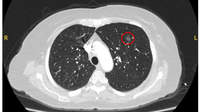

Computed tomography (CT) showing two areas (red circles) of mucoid impaction of the left upper lobe subsegmental bronchi, resulting in appearance that mimics a nodule

From the collection of Dr George Tsaknis, MD, PhD, FRCP(London), MRQA, MAcadMEd, PGCert; used with permission